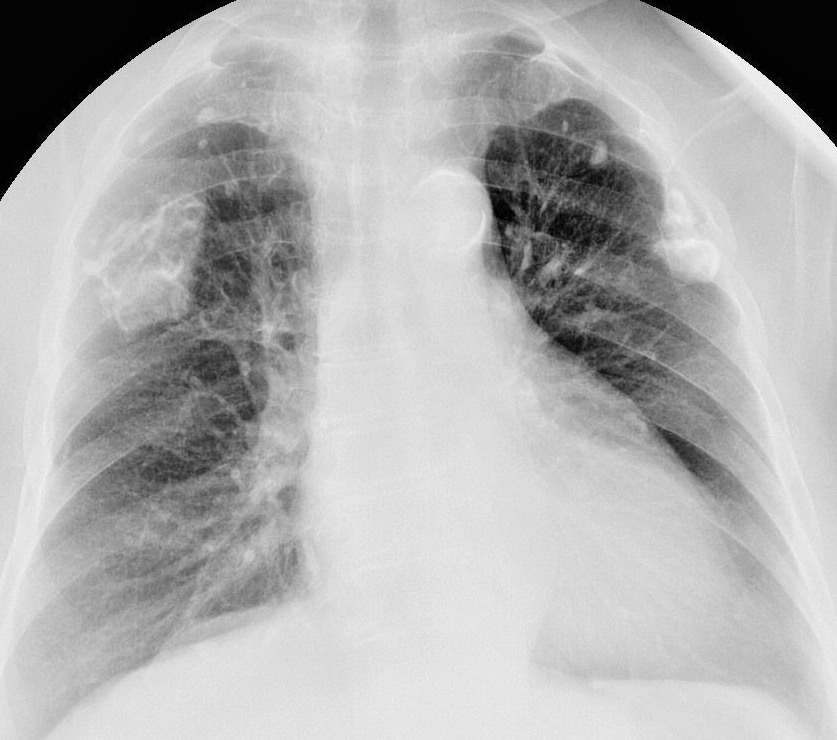

Изолированые петрификаты - в верхних долях; масивные обызествления ПЛЕВРЫ, просто такое обызествление имеет БОЛЬШУЮ толщину, чем обычные листки ...потому и как бы НАПЛЫВАЕТ на легкие. Такое мое мнение.

Болела ваша пациентка, болела точно - вот это плевральные дела - участки обызвествленной плевры.

Да, и в нижних отделах главной междолевой щели, толи осумкованные выпот, толи швартообразование.

Эта рентгеновская картина характерна для обызвествления костальной плевры.